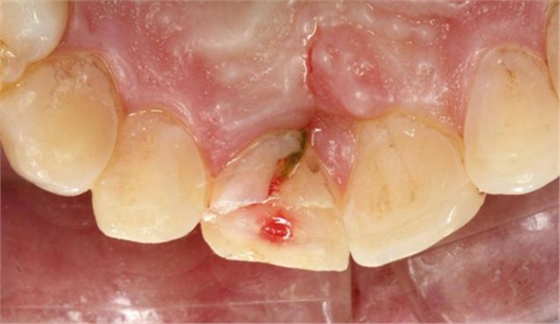

另外一例為本人高中同學(xué),同樣不慎摔倒,導(dǎo)致A1折裂,露髓,且舌側(cè)有一碎片折裂至齦下3mm左右,先看術(shù)前圖片:

首先為了粘結(jié)斷端,選擇去除牙髓,行一次性根管治療后,首先處理舌側(cè)碎片,圖中可見(jiàn)舌側(cè)碎片裂至齦下,且牙齦有明顯撕裂,如果拔除折裂片,則難以修復(fù),或者選擇牙冠延長(zhǎng)或者選擇即刻種植,本人做了一種嘗試:粘結(jié)舌側(cè)碎片,首先對(duì)位碎片,發(fā)現(xiàn)對(duì)位后非常密合,如果采用全酸蝕粘結(jié)手段,則務(wù)必要掀開(kāi)碎片,則有可能導(dǎo)致出血污染粘結(jié)面,導(dǎo)致粘結(jié)失敗。于是小心謹(jǐn)慎輕微掀開(kāi)碎片,無(wú)滲血,用最小號(hào)毛刷蘸入自酸蝕粘結(jié)劑,然后直接復(fù)位碎片,并且壓緊,讓粘結(jié)劑能均勻擴(kuò)散至斷面深處,光固化。術(shù)畢檢查,碎片粘結(jié)完好。如下圖: